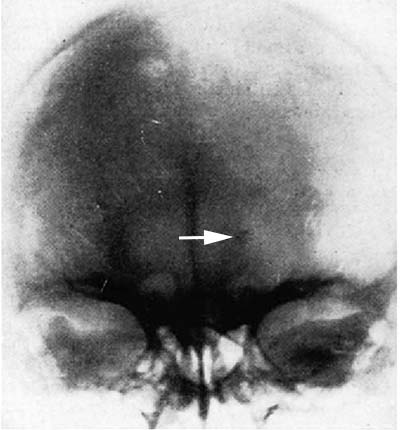

図3. 松果体の石灰化が左に偏位しており(矢印),右側に占拠性病変があることを示している[6].

X線写真による頭蓋内病変診断の試みは続いたが[→関連文献],異物や頭蓋そのものの病変を除けば病変そのものを捉えることは不可能で,頭蓋や頭蓋内石灰化におよぼす変化を間接的に診断するしかなかった.神経放射線学(Neuro-Röntgenologie) という言葉を作り,神経放射線学の父とされるオーストリアの放射線科医 Arthur Schüllerは,早くも1905年に頭蓋底の撮影法に関するモノグラフ[5]を,そして1912年に頭蓋X線撮影の包括的な教科書を著した[6].この中でSchüllerは松果体の石灰化に注目し(図3),その偏位によって頭蓋内占拠性病変の局在を推定する方法に言及しており,さらに1925年にはNaffzigerが "pineal shift" という言葉を使用してこの所見が広く知られるようになった[7].Schüllerはまた頭蓋内病変によるトルコ鞍変形,錐体骨変形などについても詳述している.Paget病に特徴的な osteoporosis circumscriptaを記載したものSchüllerである[6].ただし残念ながらこの教科書の図譜はほとんどが線画で,実際のX線写真はごく少数しか掲載されていない.このほかにも,1926年にはEdward B. Towne[8],1928年にはStenvers[9]が,それぞれ現在もTowne法,Stenvers法として使われている撮影法と,聴神経鞘腫による錐体骨のX線所見を報告している.